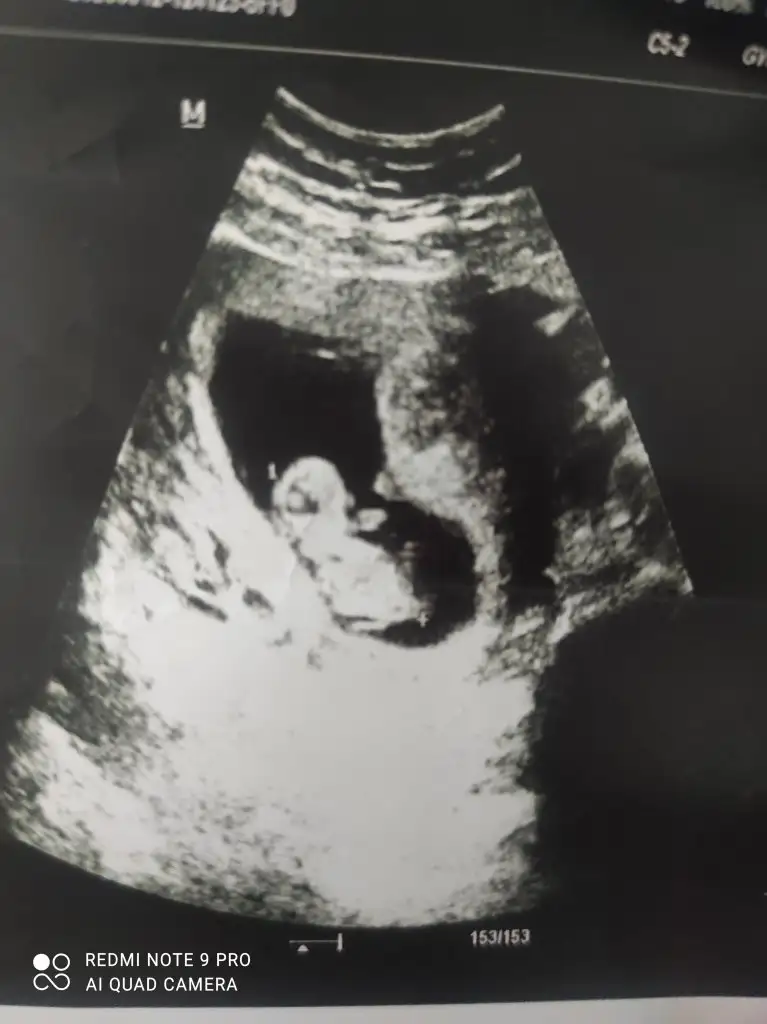

Merhaba arkadaşlar. Bugün koyu renkli kanamadan dolayı acile gittim. Bebek 10+6 olmuş. Kalp atışları da iyiydi. Rahimde bir şey görünmüyor. Ama ilk defa böyle koyu kırmızı kan gördüm. Benim durumda olan var mı? Dualarınızı bekliyorum...

Eklentiler

• IMG_20230512_155722.webp

IMG_20230512_155722.webp

23 KB · Görüntüleme: 60

Benim bundan daha az miktarda vardı .ilk 6. Haftada oldu 9. Haftada bile ultrasonda gözüküyordu bebek büyüdükçe kanama alanı küçülür ve kaybolur dediler öyle de oldu şu an 13. Haftadayım ve ultrasonda kanama alanı yok

Benim ilk defa oldu hocam, ultrasonda da birşey görünmedi. Kalp atışı da iyi dedi. Korkulacak birşey yok dedi ama içimiz hiç rahat değil :(

Ultrasonda kanama alanı görünmemesi ilginç .bana kanaman pıhtılı ve parça vs olursa sıkıntı demişti doktor. sonrasında 1.5 ay progestan kullandım ağızdan ve vajinal fitil şeklinde .kahverengi lekelenme şeklinde devam etti ve tamamen geçti.